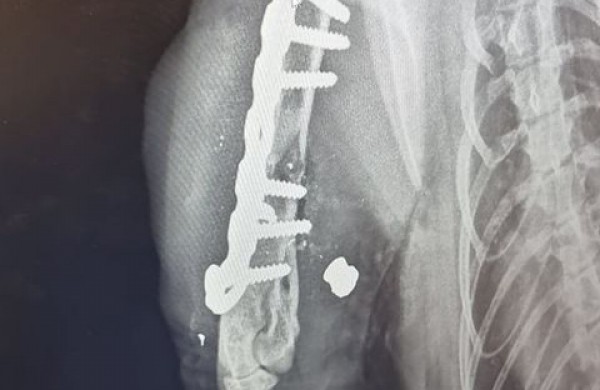

Nuvežėme katę į Jonavoje esančią veterinarijos kliniką. Atlikus rentgenogramą, išgirdome diagnozę: lūžis dėl šūvio", - istoriją nupasakojo moteris.

Šiuo metu katė jau sveiksta po operacijos, kuri truko 2,5val. Į jos koją įdėta plokštelė ir 6 varžtai. Šiai dienai gydymas kainavo 400€. Tai ,žinoma, tikrai dar nėra gydymo pabaiga", - teigė moteris.